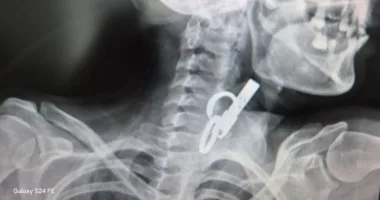

На Тернопільщині жінка тиждень ходила з дверним ключем у стравоході

У селищі Гусятин на Тернопільщині лікарі врятували життя 40-річній пацієнтці. З її стравоходу витягнули дверний ключ. Вона його проковтнула, щоб не пускати родичів у хату. До лікарні пацієнтка потрапила в шоковому стані. Медики встигли діагностували причину й оперативно провели операцію за допомогою ендоскопа без жодного розрізу. Про унікальний випадок повідомили на сторінці комунального підприємства «Гусятинська комунальна лікарня» … Читати далі На Тернопільщині жінка тиждень ходила з дверним ключем у стравоході